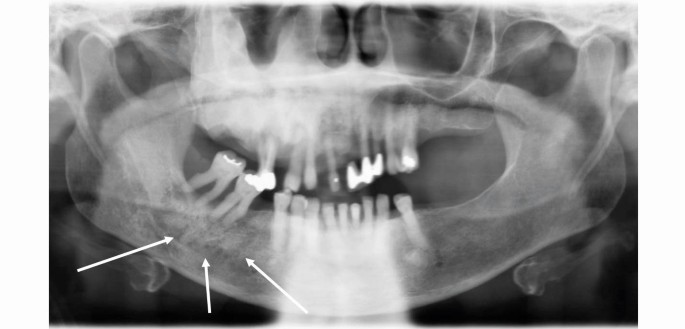

Figure 3 and Figure 4 show the radiographic appearance and CBCT of the jaws, confirming the bony appearance and expansion.

Case 1: orthopantomogram showing the typical ‘ground-glass' and mixed mottled appearance (indicated with arrows), unerupted teeth, taurodont molars, short roots and poorly defined lamina dura and inferior dental canal

The ‘ground-glass' radiographic appearance of the bone in the right maxilla and mottled appearance in the lower right mandible are evident in Figure 11.

Case 2: orthopantomogram showing the ground-glass and mottled appearance of the alveolar bone (indicated with arrows) and generalised horizontal bone loss